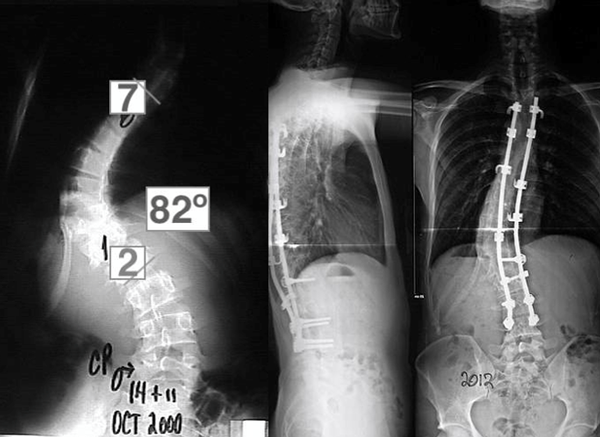

La malformación de Chiari tipo I permaneció sin cambios, pero se observó una progresión de la curva escoliótica a 350°. A la edad de 12 años y 3 meses, el paciente fue intervenido quirúrgicamente de la malformación de Chiari tipo I.

Se realizó un abordaje con craniectomía suboccipital asociada a resección del arco posterior en C1. Dos años más tarde, se constató que dicha escoliosis había progresado a 82° (Figura 3) y se decidió hacer la fusión espinal posterior instrumentada de T4-L4 con corrección de la curva a 390°.

Figura 3. Espinograma, frente. Progresión curva de Cobb y su corrección mediante instrumentación toraco-lumbar.